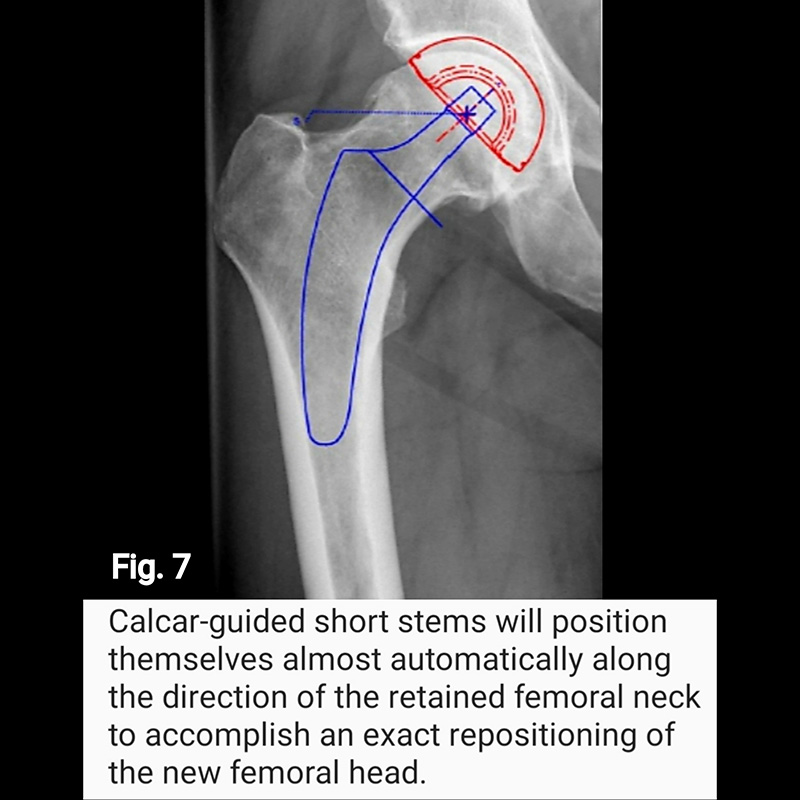

Short stems offer numerous advantages. First, with some short stem designs, a majority of the femoral neck is preserved. Surgically, this requires less surgical dissection and mitigates soft tissue and bone damage. Retaining the femoral neck has significant mechanical advantage in reducing both axial and torsional loads, as well as restoring the center of rotation of the femoral head in the sagittal plane (respect the anterior offset) improving hip balance (Fig. 6), and in the coronal plane (respect horizontal offset) improving abductor strength (Fig. 7 and Fig. 8). Ultimately, preservation of the femoral neck provides a more natural barrier to migration of particulate debris, is associated with less blood loss and less time and energy to rehabilitate the hip, reduces stress shielding of the proximal femur (i.e., load redistribution and subsequent loss of proximal femoral bone mass) (Fig. 9), and reduces end-of-stem thigh pain (spot weld Fig.9).